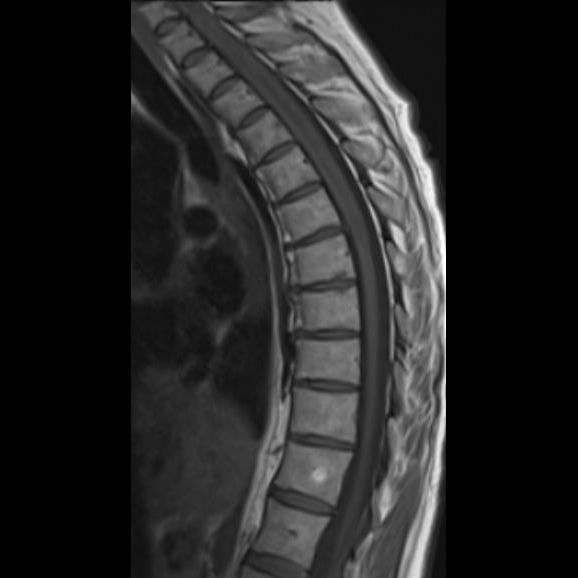

- (A) Torakal MRG’de sagital görüntülerde üst-orta torakal düzeyde T2A hiperintens (oklar), T1A izo-hipointens (ok) uzun segment ekspansil sinyal değişikliği izlenmekte olup sagital postkontrast T1A’da kontrast tutulumu mevcuttur (oklar). Bulgular longitudinal ekstensif transvers miyelit (LETM) ile uyumludur.

- Transvers miyelit sıklıkla santral gri cevheri etkileyen ve üç veya daha fazla vertebral gövde uzunluğunu etkilemektedir (LETM).

- Transvers kesitlerde, santral kordu tutma eğilimindedir.

- Omurilik atrofisi ve ekspansiyon/ödem MS’e göre daha fazla görülür.

- Kontrast madde enjeksiyonu sonrasında neredeyse tüm akut NMO lezyonları, yamalı, düzensiz veya periferik olarak kontrastlanma gösterir.